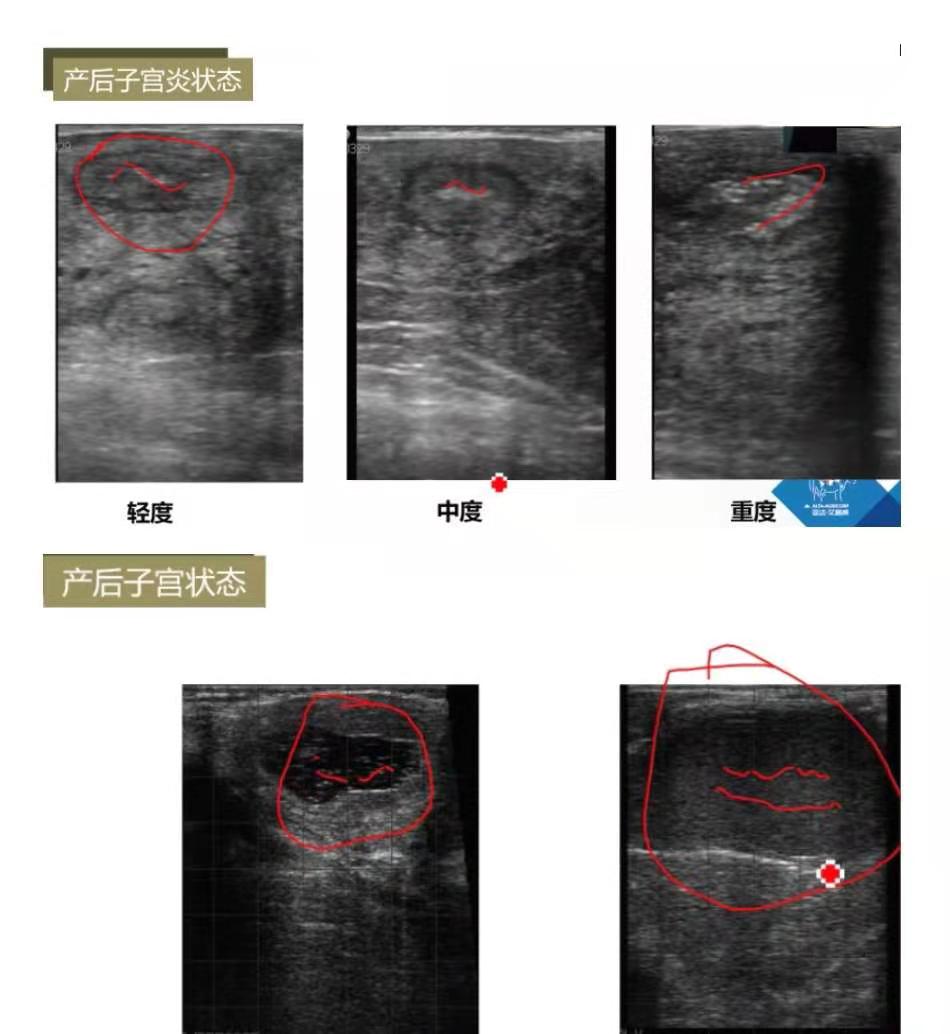

产后子宫炎:产后21天内称为子宫炎,21天后称为子宫内膜炎。评估时间产后24-30天。轻度子宫角雪花状点状,面积越大炎症反应越重

产后子宫状态:子宫内有积液